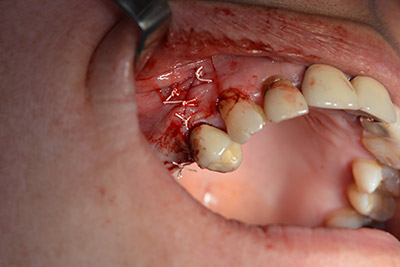

La paciente de 59 años presentaba una periodontitis avanzada, describía una desagradable sensación y un mal gusto proveniente del primer cuadrante. La evaluación clínica mostró en general marcadas profundidades de bolsa y una degeneración ósea muy avanzada en las regiones 16 y 14. El estudio radiológico corroboró estos resultados (figura 1). Las piezas dentales 16 y 14 no podían conservarse.

Una membrana reabsorbible formó la barrera en sentido bucal y cubrió el aumento. Por último se procedió a la sutura de modo que no penetrara saliva (figuras 15 a 19).